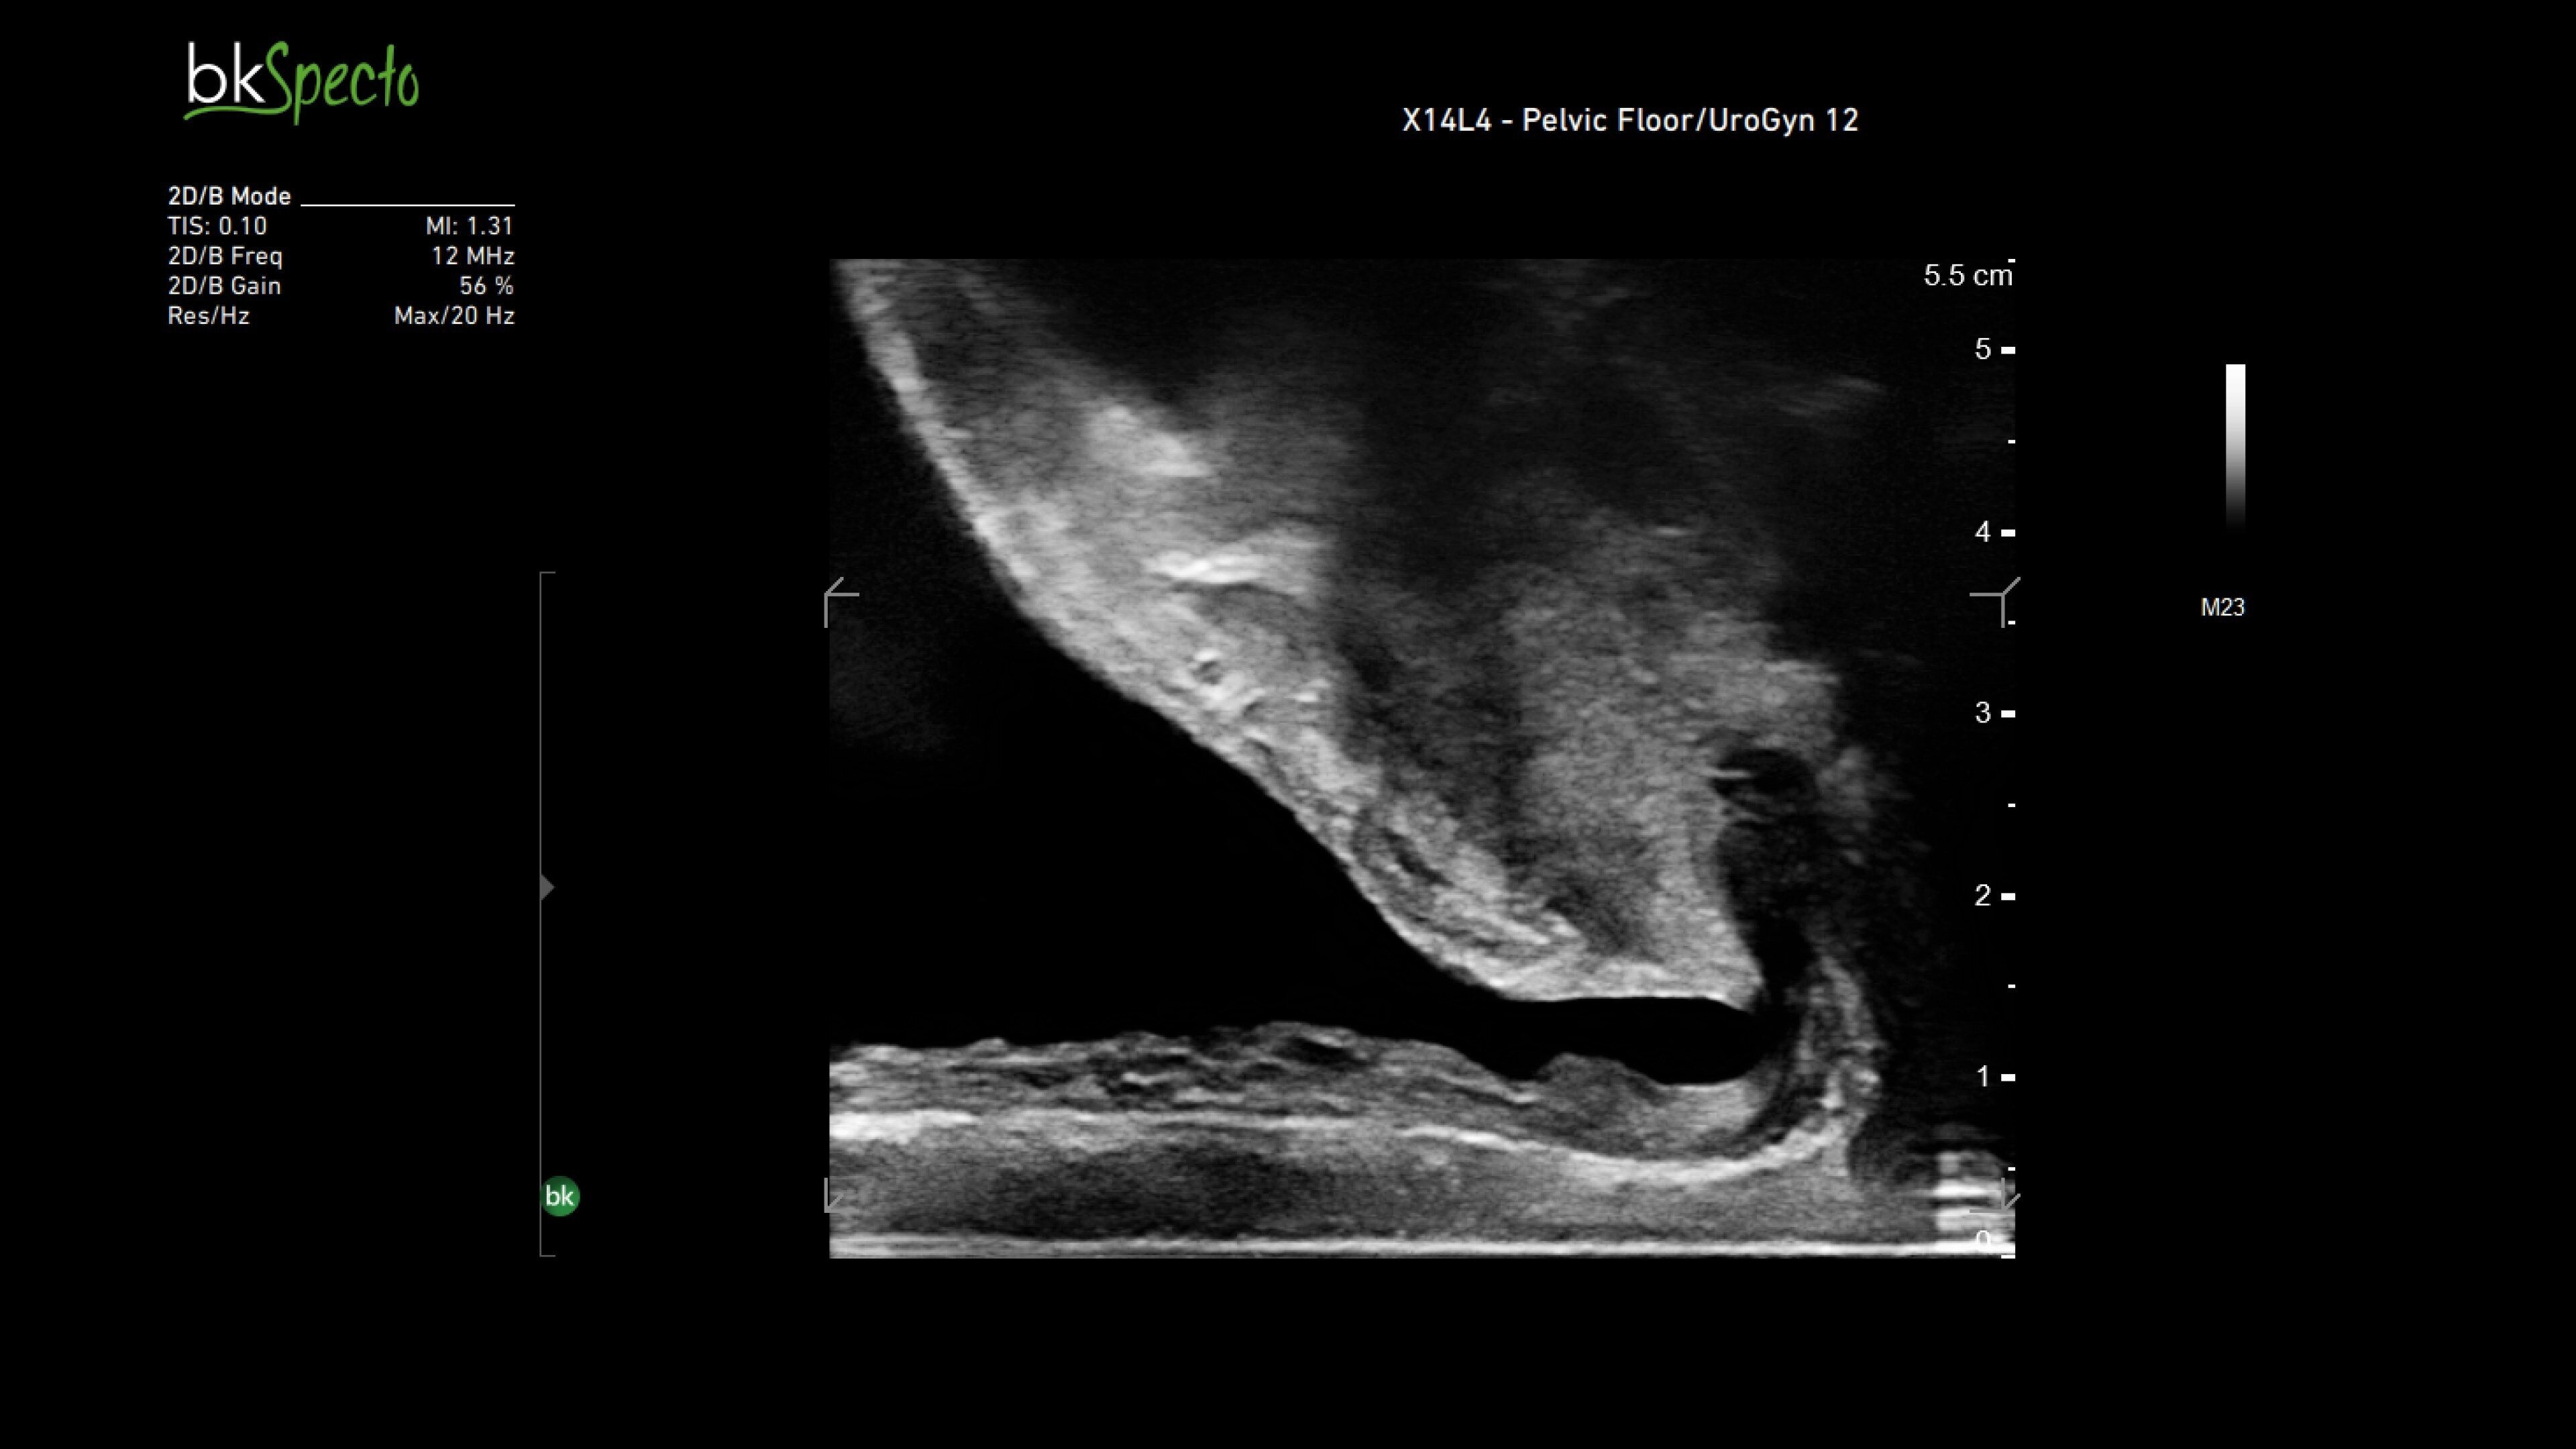

General surgery

Enhanced visualization for general surgery

The bkActiv ultrasound system delivers remarkable imaging for general surgery, including anorectal, robotics-assisted, and pelvic floor surgeries. Its advanced algorithms provide uniform image resolution and greater detail, while the remote control allows surgeons to adjust images within the sterile field. For anorectal surgeries, bkActiv offers high-definition imaging to visualize normal and abnormal anatomy, including anal sphincter injuries and rectal cancer. In robotics-assisted surgeries, the system's robotic transducers provide real-time, high-resolution imaging to locate and assess lesions and critical structures. For pelvic floor surgeries, bkActiv's advanced 3D architecture supports dynamic, real-time examination during procedures.